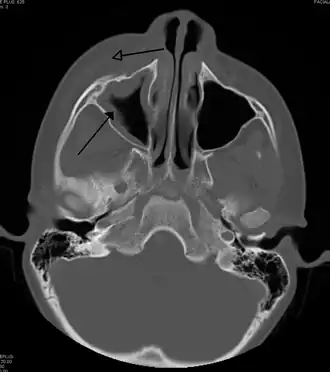

For sinusitis lasting more than 12 weeks, a CT scan is recommended.[66] On a CT scan, acute sinus secretions have a radiodensity of 10 to 25 Hounsfield units (HU). In a more chronic state, they become more viscous, with a radiodensity of 30 to 60 HU.[69]

-

CT of chronic sinusitis -

CT scan of chronic sinusitis, showing a filled right maxillary sinus with sclerotic thickened bone -